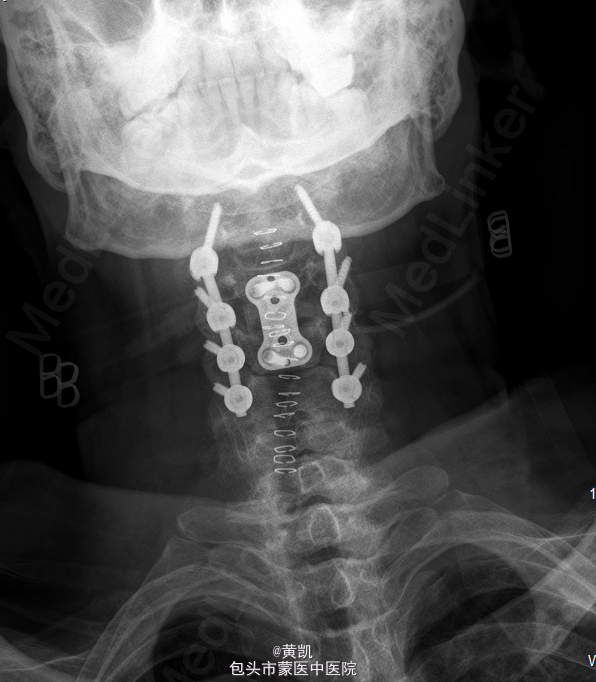

初步诊断:1.颈椎结核 2.胸椎结核 3.2型糖尿病.处理:行“颈椎前路结合病灶清除植骨融合内固定术+取髂骨植骨术+颈椎后路内固定术”。

手术顺利,术后恢复可,切口愈合佳,无明显渗出。目前一般情况可,生命体征平稳,切口愈合佳。